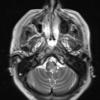

MYELIN (IMMUNE-MEDIATED)

Inflammatory Demyelination (19)